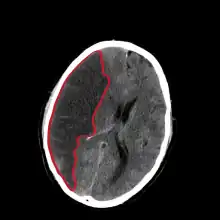

| CT scan slice of the brain showing a right-hemispheric cerebral infarct (left side of image). | |

Computed tomography (CT) and MRI scanning will show damaged area in the brain. A CT scan will rule out a hemorrhagic stroke, is cheaper for the patient, and can be found in almost all hospitals unlike an MRI machine.[26][27] Once the Doctor rules out a hemorrhagic stroke, rTPA can be given.[26] An MRI can help to diagnose an acute cerebral infarct as quickly as 6 hours from start of symptoms,[26] It can also help time when the stroke happened.[28] The biggest problem with an MRI is it can't be done on a patient with certain metallic implants or if the patient is claustrophobic.[29] A head and neck CT angiogram can be performed within 6 hours of onset of symptoms to see where the occlusion may be located which can help in determining the cause of the stroke.[30] In people who die from a stroke an autopsy can reveal additional diseases or conditions beyond the stroke itself, as well as uncover uncommon causes of a stroke.[31]